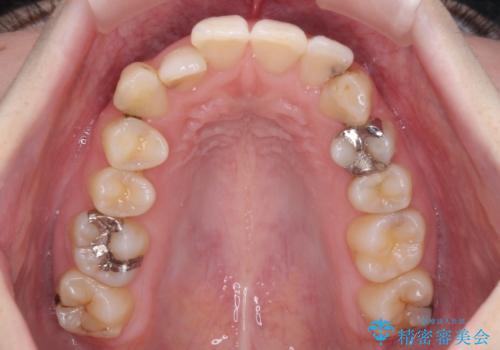

- 前歯のデコボコをクロスバイトを気にして来院された患者様です。

上顎骨の横幅が狭く、上下ともに内側に倒れ込んだ混み合った歯列となっていました。

矯正治療後には、目立つ銀歯と隣接するむし歯をセラミックインレーにて修復治療することとしました。